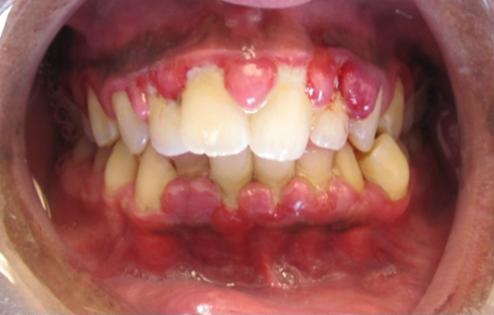

Gingivitis adalah penyakit gusi yang merupakan sejenis keradangan yang berlaku di bahagian gusi disebabkan oleh plak bakteria yang terkumpul di sekitar gigi dan gusi. Tanda-tanda utama gingivitis termasuk gusi yang bengkak, mudah berdarah apabila memberus gigi, serta rasa tidak selesa di kawasan mulut. Jika tidak dirawat, keadaan ini boleh berlarutan dan berkembang menjadi penyakit yang lebih serius.